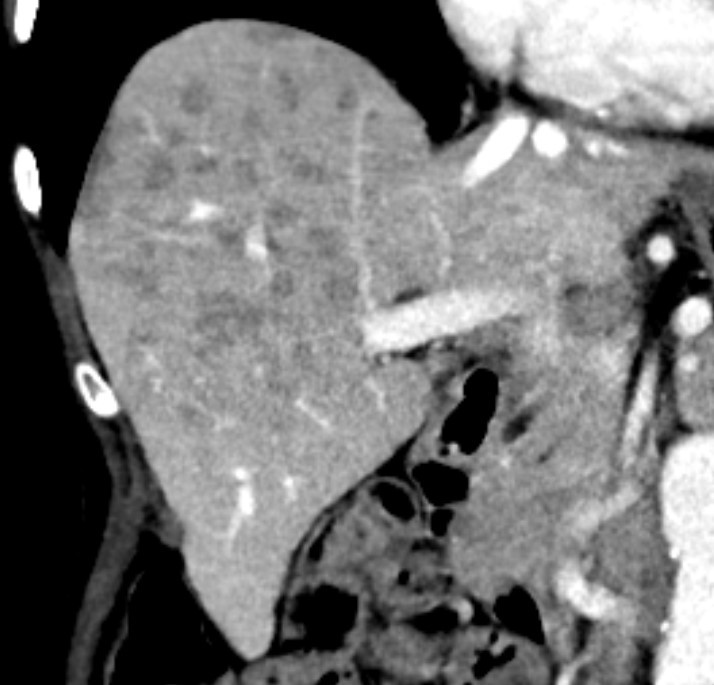

Til venstre ses leveren på et T1-vektet MR-bilde i inn-av-fase-sekvens hos en kvinne i slutten av 70-årene med seropositiv revmatoid artritt, polymyositt og polynevropati. Hun var henvist av fastlegen på grunn av magesmerter og vekttap fra 60 kg til 46 kg de siste tre årene. Bildet til høyre viser ut-av-fase-sekvensen med multiple lavintense leverlesjoner forenelig med tilstedeværelse av fett (1). I regi av fastlegen var det tidligere tatt en CT abdomen med intravenøs kontrastvæske, som viste multiple velavgrensede, lavattenuerende lesjoner uten ekspansive trekk i høyre leverlapp, som ga mistanke om levermetastaser.

Fettholdige leverlesjoner kan representere steatose, hepatocellulære adenomer, hepatocellulære karsinomer og i sjeldne tilfeller metastaser. Lesjonene var lett hyperintense på T2-vektet sekvens, viste ingen diffusjonsrestriksjon og var lavintense på T1-sekvensene etter kontrastmiddel. Disse signalkarakteristikaene gjorde at multifokal nodulær leversteatose var den mest sannsynlige diagnosen. Leverbiopsi viste kronisk portal og lett periportal betennelse med eosinofili samt steatose og steatohepatitt. Funnene kunne være forenlig med medikamentindusert leverskade. Pasienten hadde brukt metotreksat i mange år, som kan forårsake leversteatose og -fibrose. I samråd med revmatolog ble metotreksat seponert.

Multifokal nodulær steatose er en sjelden presentasjon av leversteatose som ofte vekker mistanke om primær eller sekundær malign leversykdom. MR av lever er anbefalt for karakterisering og vil typisk vise signalbortfall i lesjonene på ut-av-fase T1-vektet MR. Ultralyd med kontrast kan også gi diagnosen i noen tilfeller (2). Når diagnosen kan stilles med høy grad av sikkerhet ved bildediagnostikk, kan biopsi unngås. Lesjonene kan da følges opp radiologisk (3).